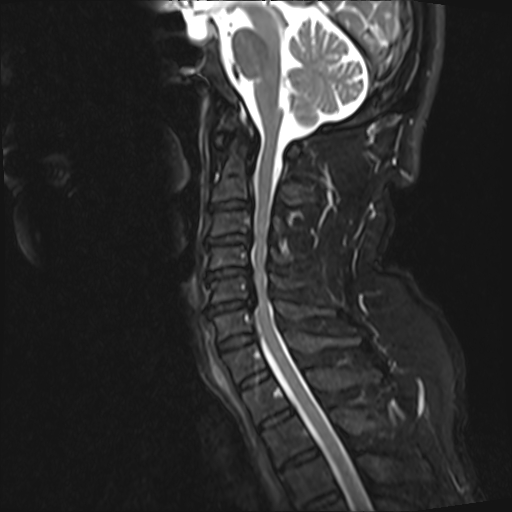

术后第三天病人可下床行走,自觉行走不稳及双手精细动作较术前明显改善,查体见四肢肌力、肌张力、胸腹部束带感及各病理阳性体征均有改善。术后复查影像满意,住院15天后,效果满意,顺利出院。

术后CT见减压充分,螺钉位置良好